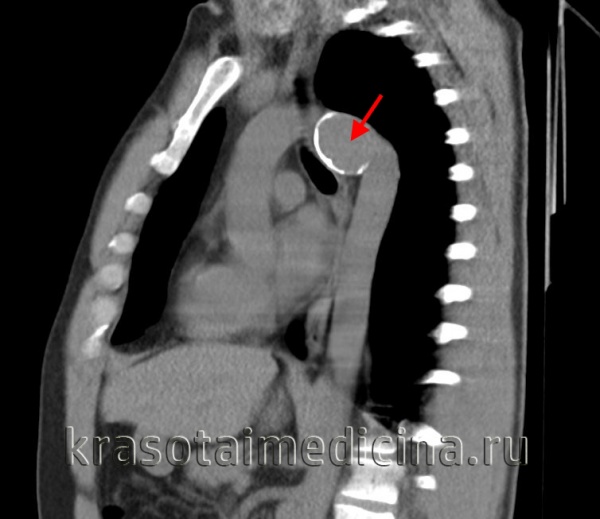

КТ-ангиография аорты. Аневризма брюшной аорты над бифуркацией. Просвет аневризмы (красная стрелка), пристеночный тромб (зеленая стрелка).

- Компьютерная томография. КТ (МСКТ) грудной/брюшной аорты позволяет точно и наглядно представить аневризматическое расширение, выявить наличие расслоения и тромботических масс, парааортальной гематомы, очагов кальциноза.